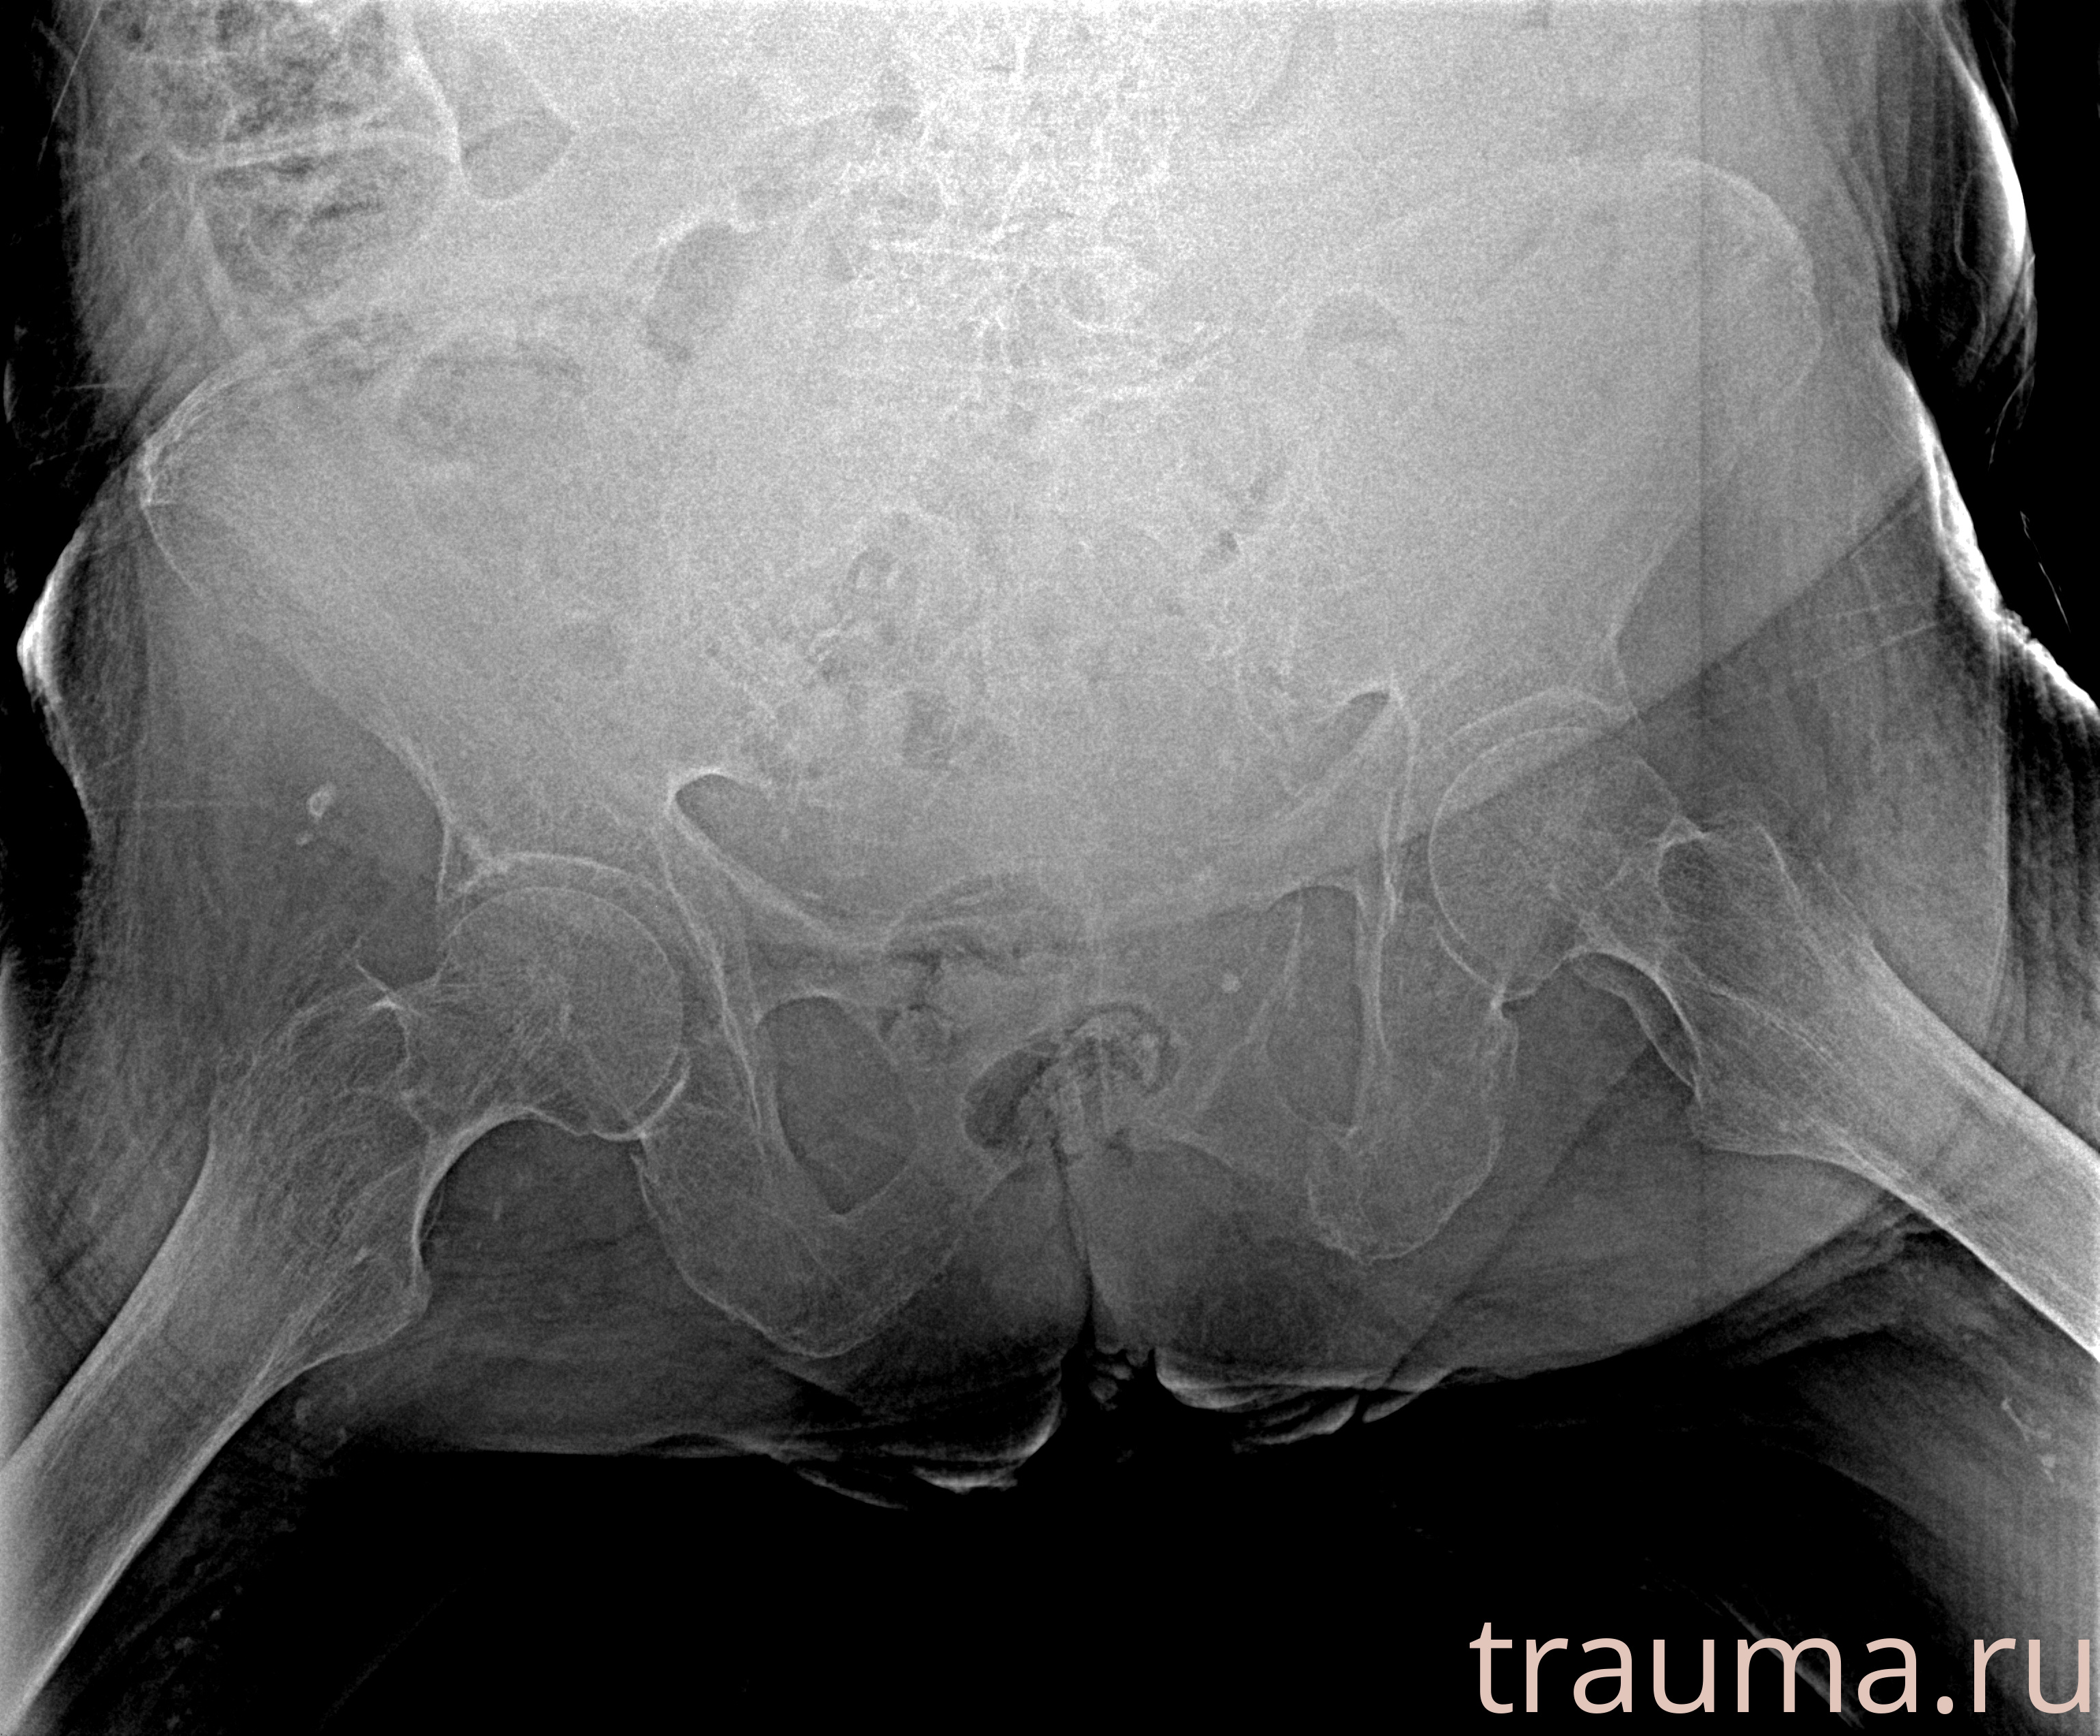

Рентгенограммы

Рентген на дому: по вашему адресу приезжает врач-рентгенолог, травматолог-ортопед с мобильным рентгеновским аппаратом, проводит диагностику травмы или заболевания, делает необходимые рентгенограммы, дает рекомендации по дальнейшему лечению. Получить качественные снимки в домашних условиях возможно благодаря уникальной методике, разработанной МосРентген Центром для института  Склифосовского